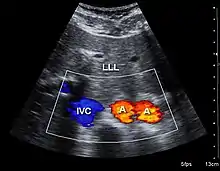

Imagerie médicale

En imagerie médicale, les artefacts sont de fausses représentations de structures tissulaires vues dans les images médicales que l'échographie, la tomodensitométrie à rayons X et imagerie par résonance magnétique. Ces artefacts peuvent être causés par une variété de phénomènes tels que la physique sous-jacente de l'interaction énergie-tissu, les erreurs d'acquisition de données (telles que les mouvements du patient) ou l'incapacité d'un algorithme de reconstruction à représenter correctement l'anatomie. Les médecins apprennent généralement à reconnaître certains de ces artefacts pour éviter de les confondre avec une pathologie réelle.